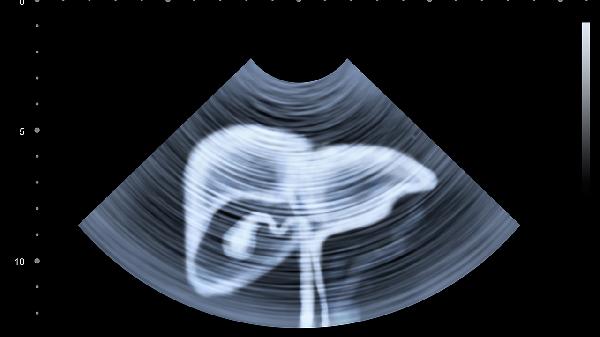

肝脏没有痛觉神经,等出现明显症状时往往为时已晚。建议40岁以上人群每年做一次肝脏超声和肝功能检查,有肝炎病史的更要加强监测。从现在开始改掉那些伤肝的睡前习惯,别让沉默的肝脏独自承受伤害。好好爱护这个任劳任怨的"解毒工厂",它才能继续为我们健康工作几十年。